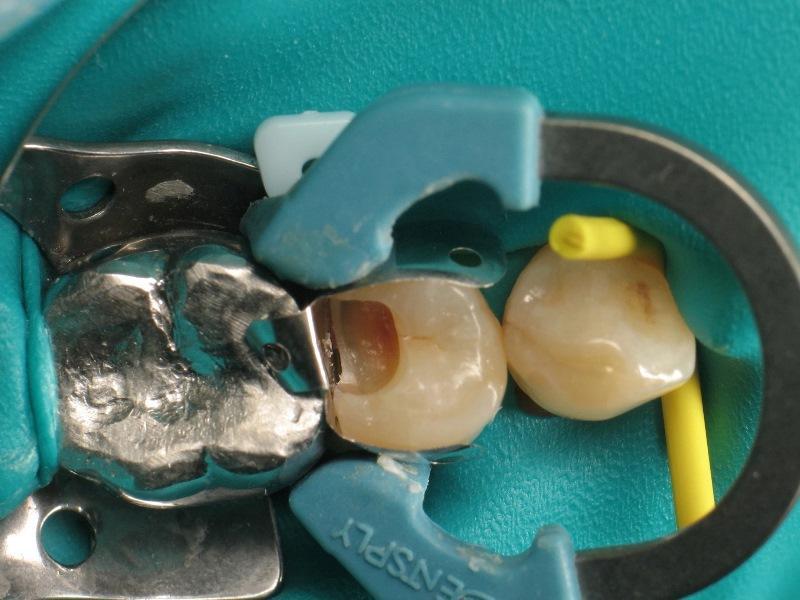

Фото 2: Наложение коффердама.